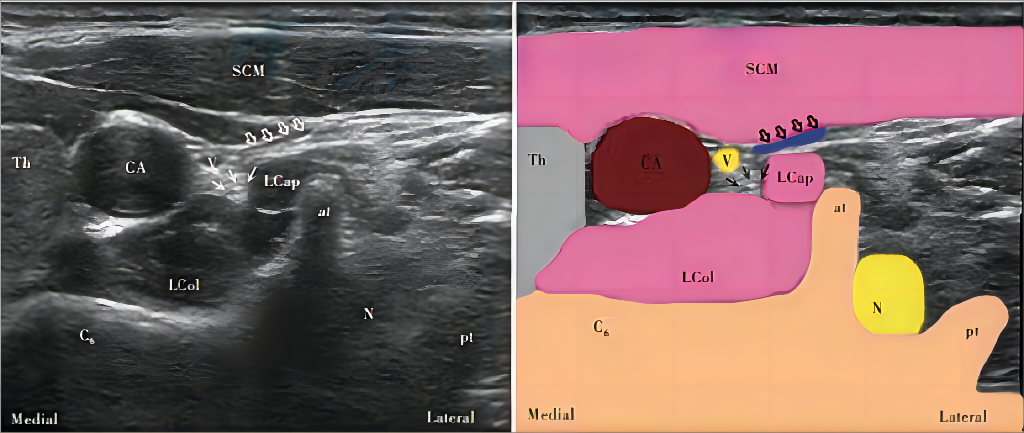

超声下C6椎体水平短轴超声图像及其示意图[3]

(图4来源:星状神经节阻滞疗法中国专家共识2022版)

SCM 为胸锁乳突肌,CA为颈总动脉,Th为甲状腺,C6为第6颈椎,LCol为颈长肌, LCap为头长肌,at为横突前结节,pt为横突后结节,N为颈6神经根;实心箭头为颈交感链,空心箭头为压闭的颈内静脉;Medial为内侧,Lateral为外侧